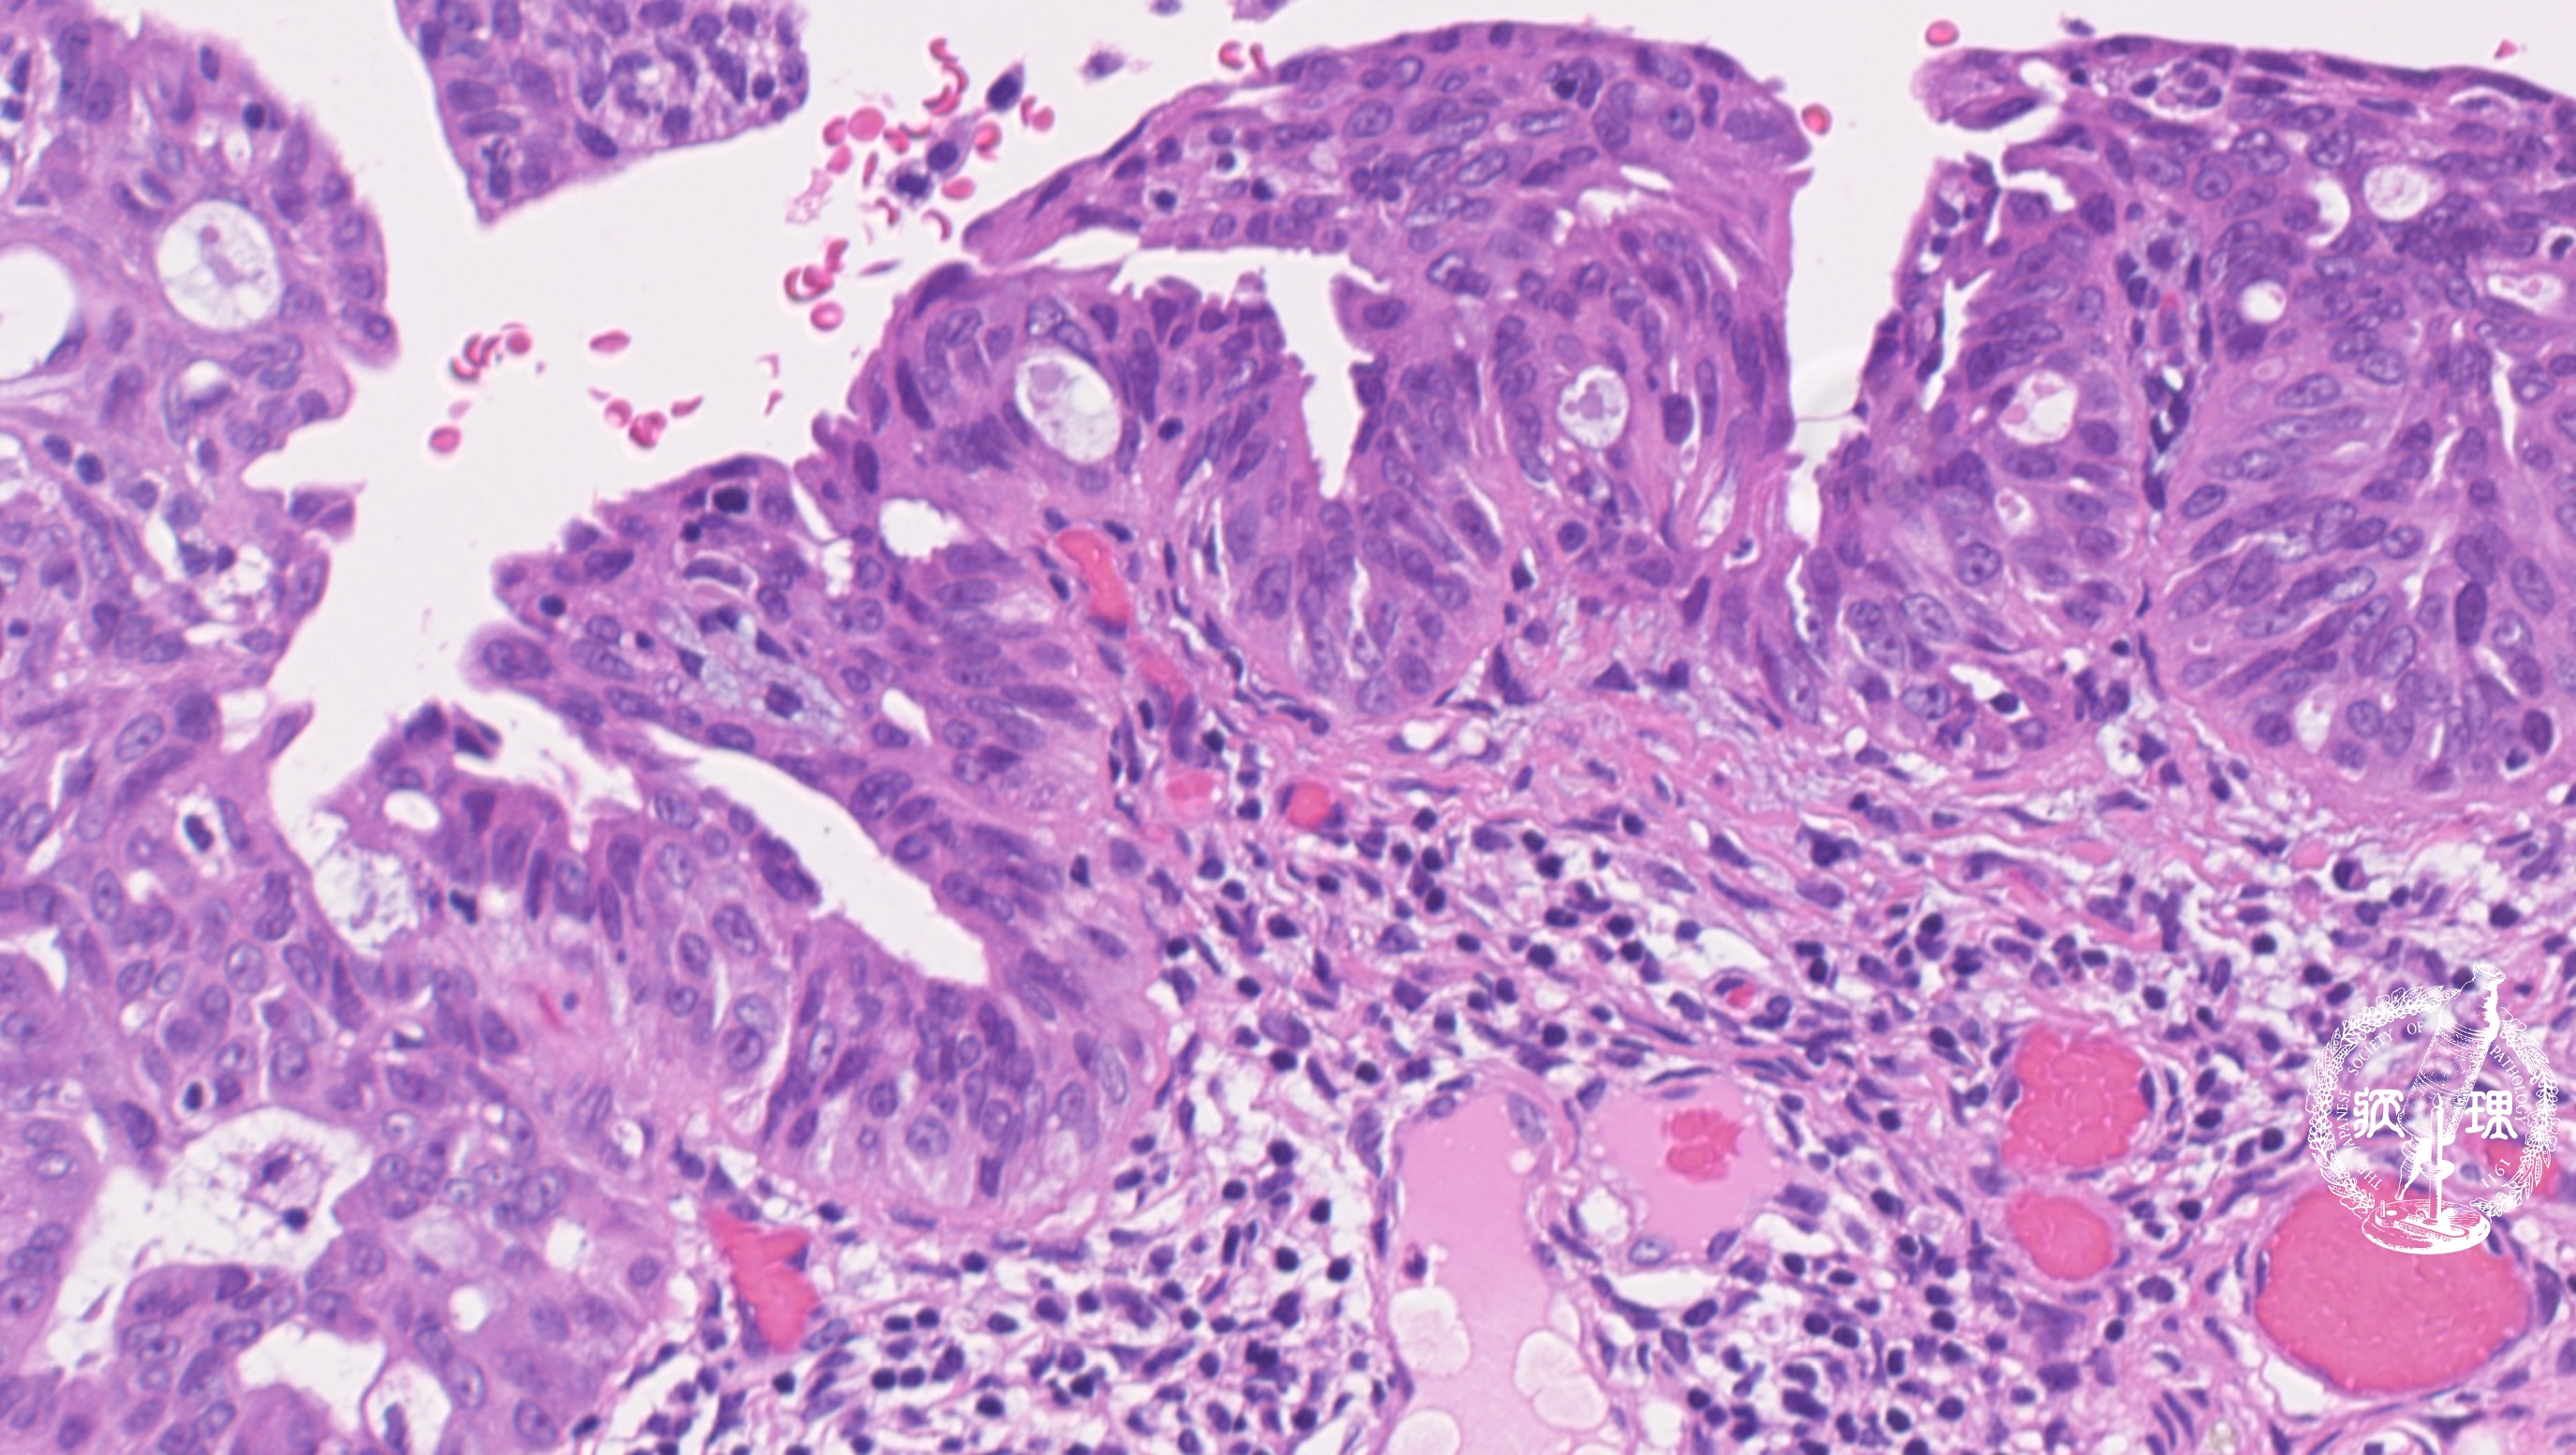

ミクロ像 (HE弱拡大):卵管采上皮。既存の卵管采上皮を置換するように、濃染腫大核を有する腫瘍細胞が密に増生している。左側には正常の卵管上皮 が残存している(矢印)。